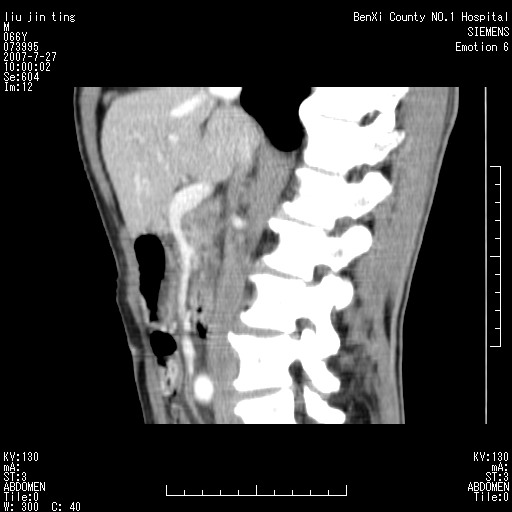

腹痛,背痛,无恶心呕吐,不黄,彩超示胰腺钩癌,ct扫描病灶平扫30-40hu,增强后动脉期40--60hu,静脉期50-68hu,真的是钩突上的么?您要试一试么?

动脉期

静脉期